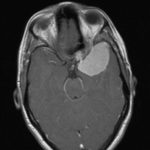

Cette masse peut entrainer notamment :

- Une irritation du cerveau qui se manifeste par une épilepsie

- Une compression voire destruction d’une partie du cerveau causant un affaiblissement ou une perte d’une fonction du cerveau

- Une augmentation de la pression à l’intérieur du crâne (espace inextensible à l’intérieur duquel vient s’ajouter le volume de la tumeur), ce qui va se manifester initialement par des maux de tête d’aggravation progressive qui vont s’associer à des nausées, des vomissements, des troubles visuels… Cet état peut aboutir à la perte de la vue dans les formes d’évolution lente et au décès dans les formes d’évolution rapide.